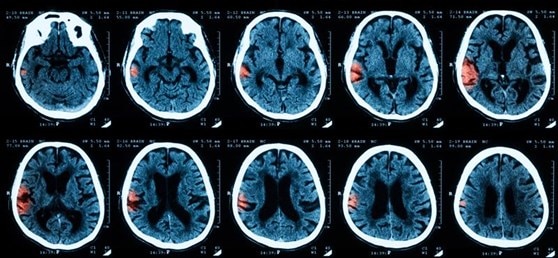

Analyzing neural imaging with learning models

Brain scanning modalities, such as magnetic resonance imaging (MRI) and positron-emission tomography (PET), are invaluable tools for diagnostics and translational research on brain function and disease [4]. However, the inherent complexity and subtlety of a single brain scan can make it challenging for clinicians to accurately assess neurological conditions [5]. AI learning models are starting to study libraries of previous diagnostic cases and analyze huge amounts of data in extremely fine detail. These models can then recognize patterns in the images and better identify lesions or abnormal activity, which can help confirm diagnoses and predict the best treatment avenues on a patient-to-patient basis. Deep neural networks have been implemented to speed up acquisition of MRI data, enhance signal-to-noise ratio (SNR) and resolution, reconstruct and register brain images, and even optimize radiation dosage for advanced processes like theranostic CT scanning [6, 7, 8].

AI-based brain imaging software in development. Machine learning analysis of CT-scans predicts a lesion from patient data very quickly, with high accuracy.